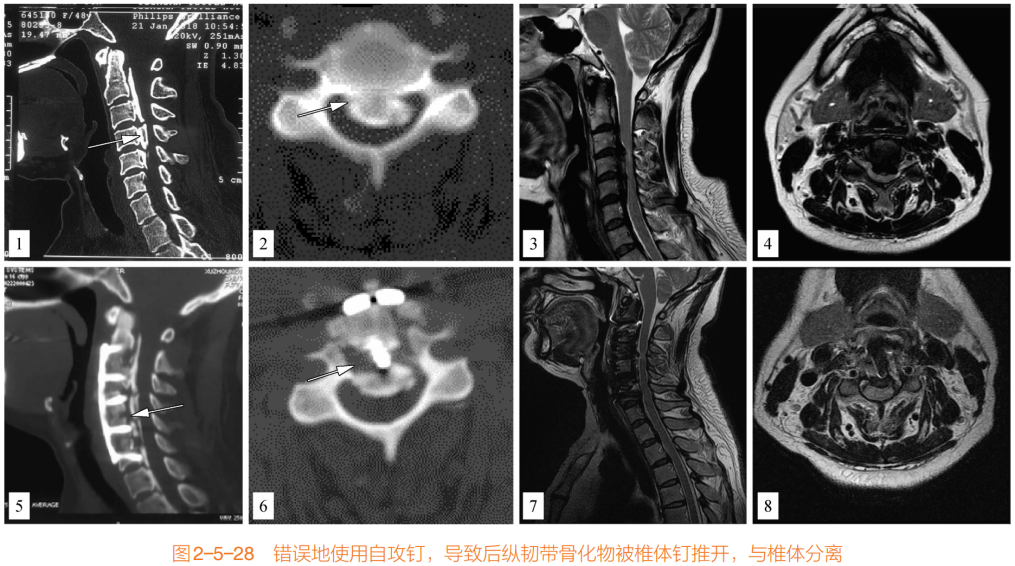

(三)自钻螺钉

1、自钻螺钉因其头部尖锐,较容易钻入椎体后的骨化物中,形成较强的把持力,相较于自攻螺钉具有明显优势。自攻螺钉头部圆钝,难以攻入致密的后纵韧带骨化物中,甚至存在使椎体和骨化物分离的风险。